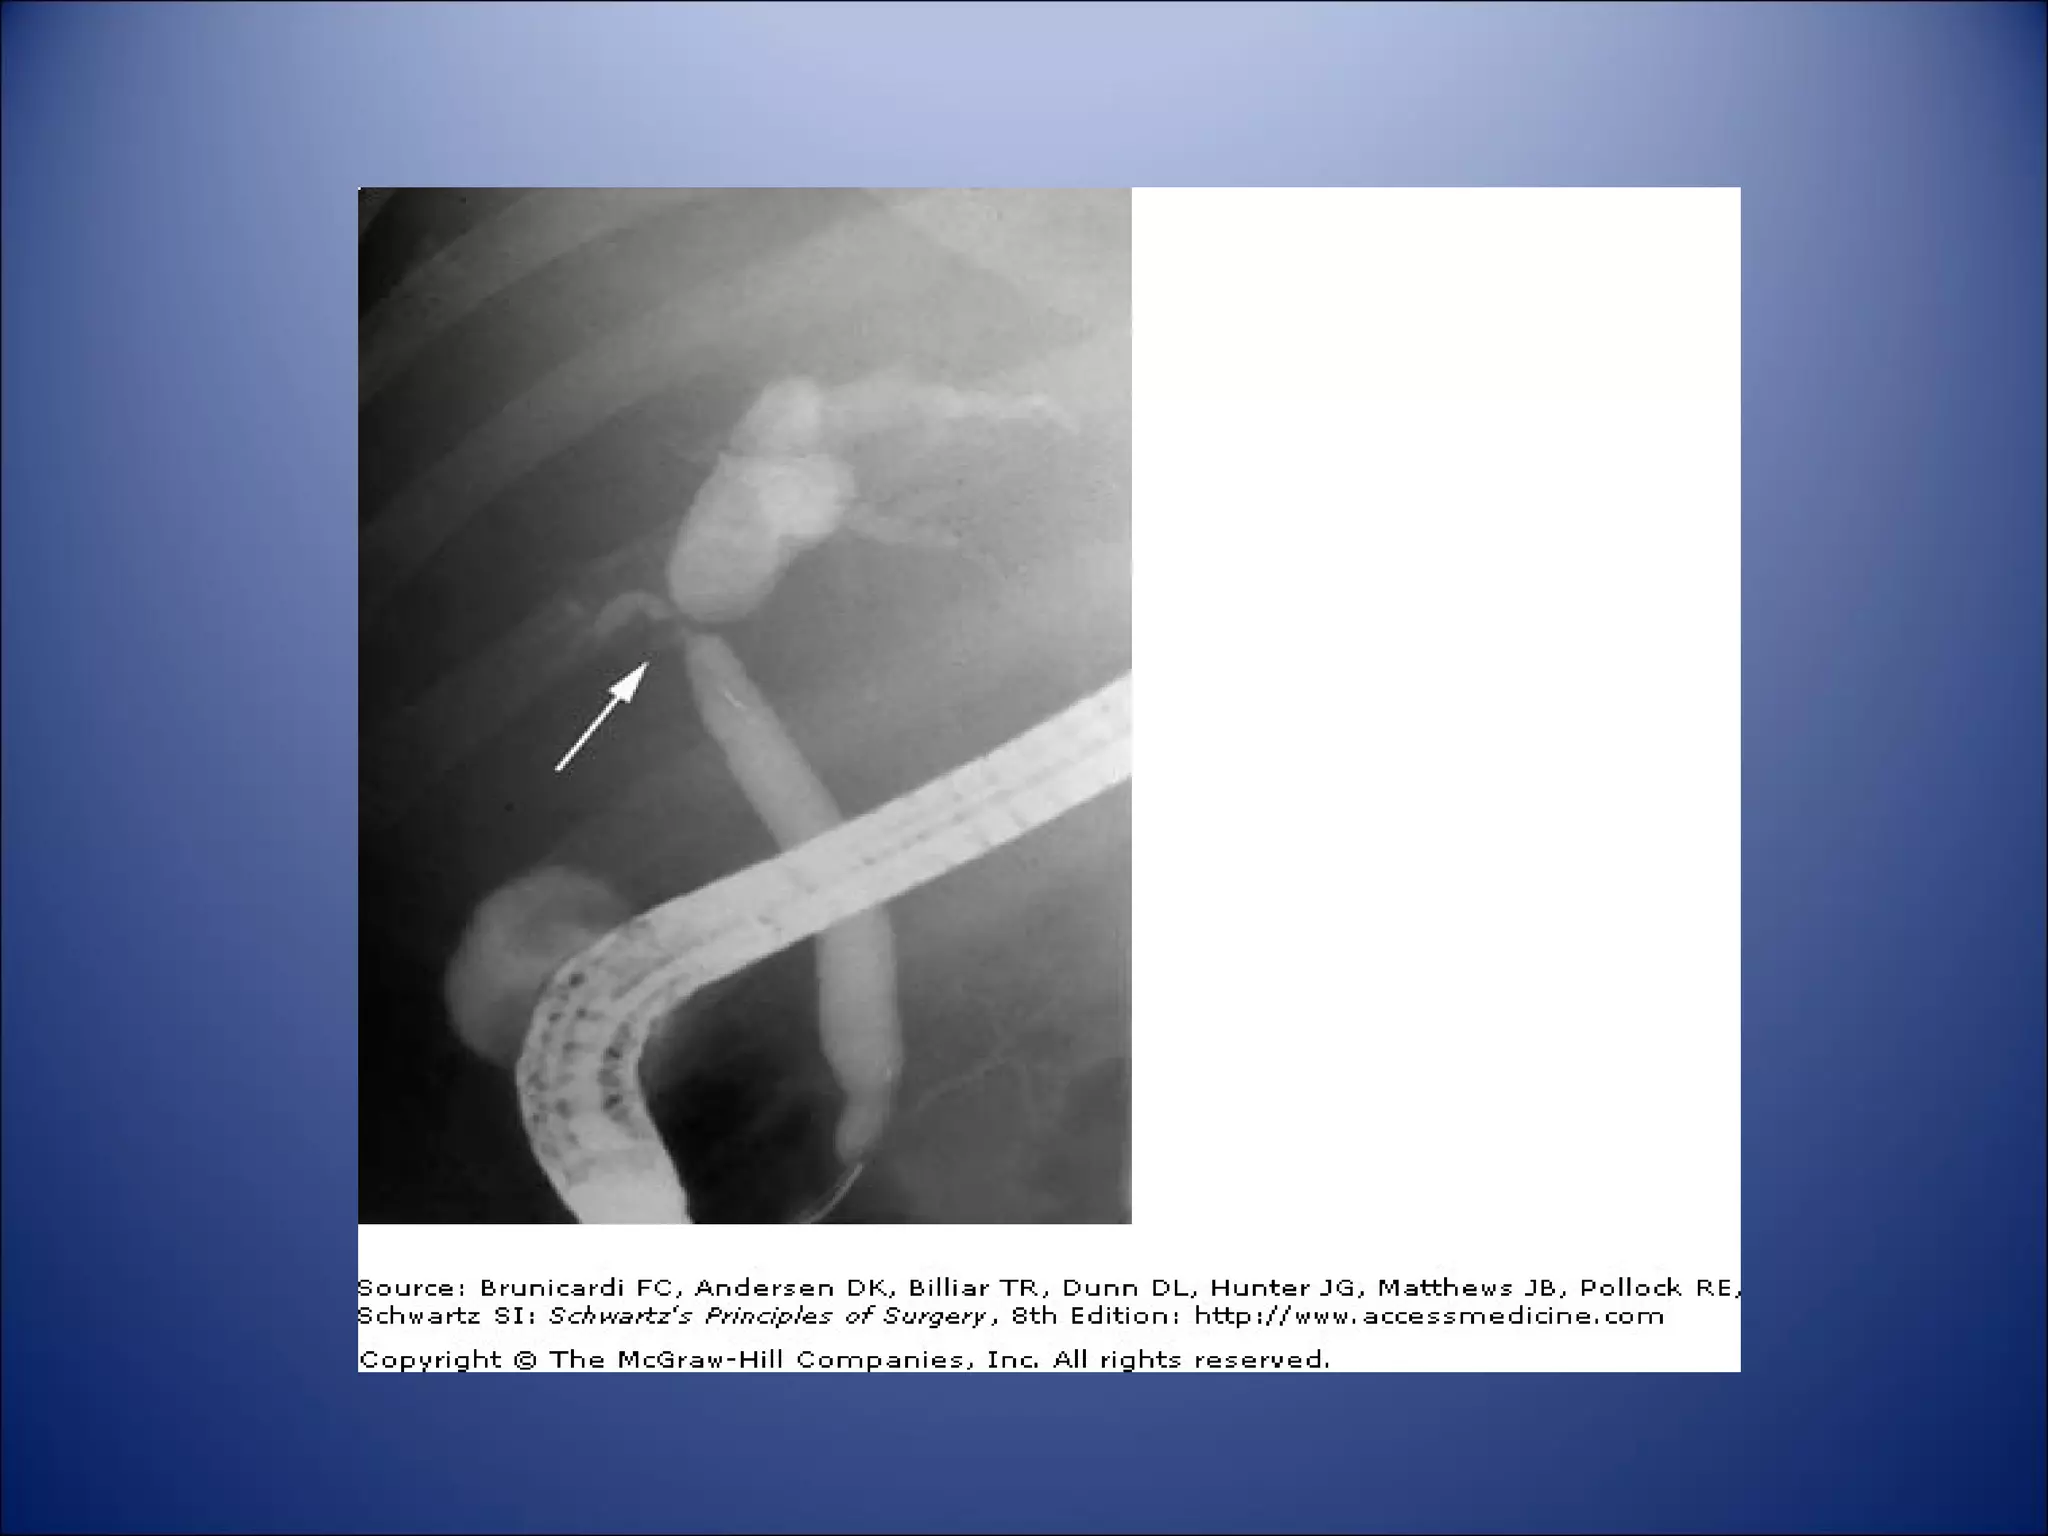

ERCP:

 Require pt sedation.

 Direct visualization of the ampullary region and direct access to the distal CBD.

 Can be used for therapeutic intervention.

 Used mainly to evaluate complicated duct stones.

 Complications include pancreatitis and cholangistis.